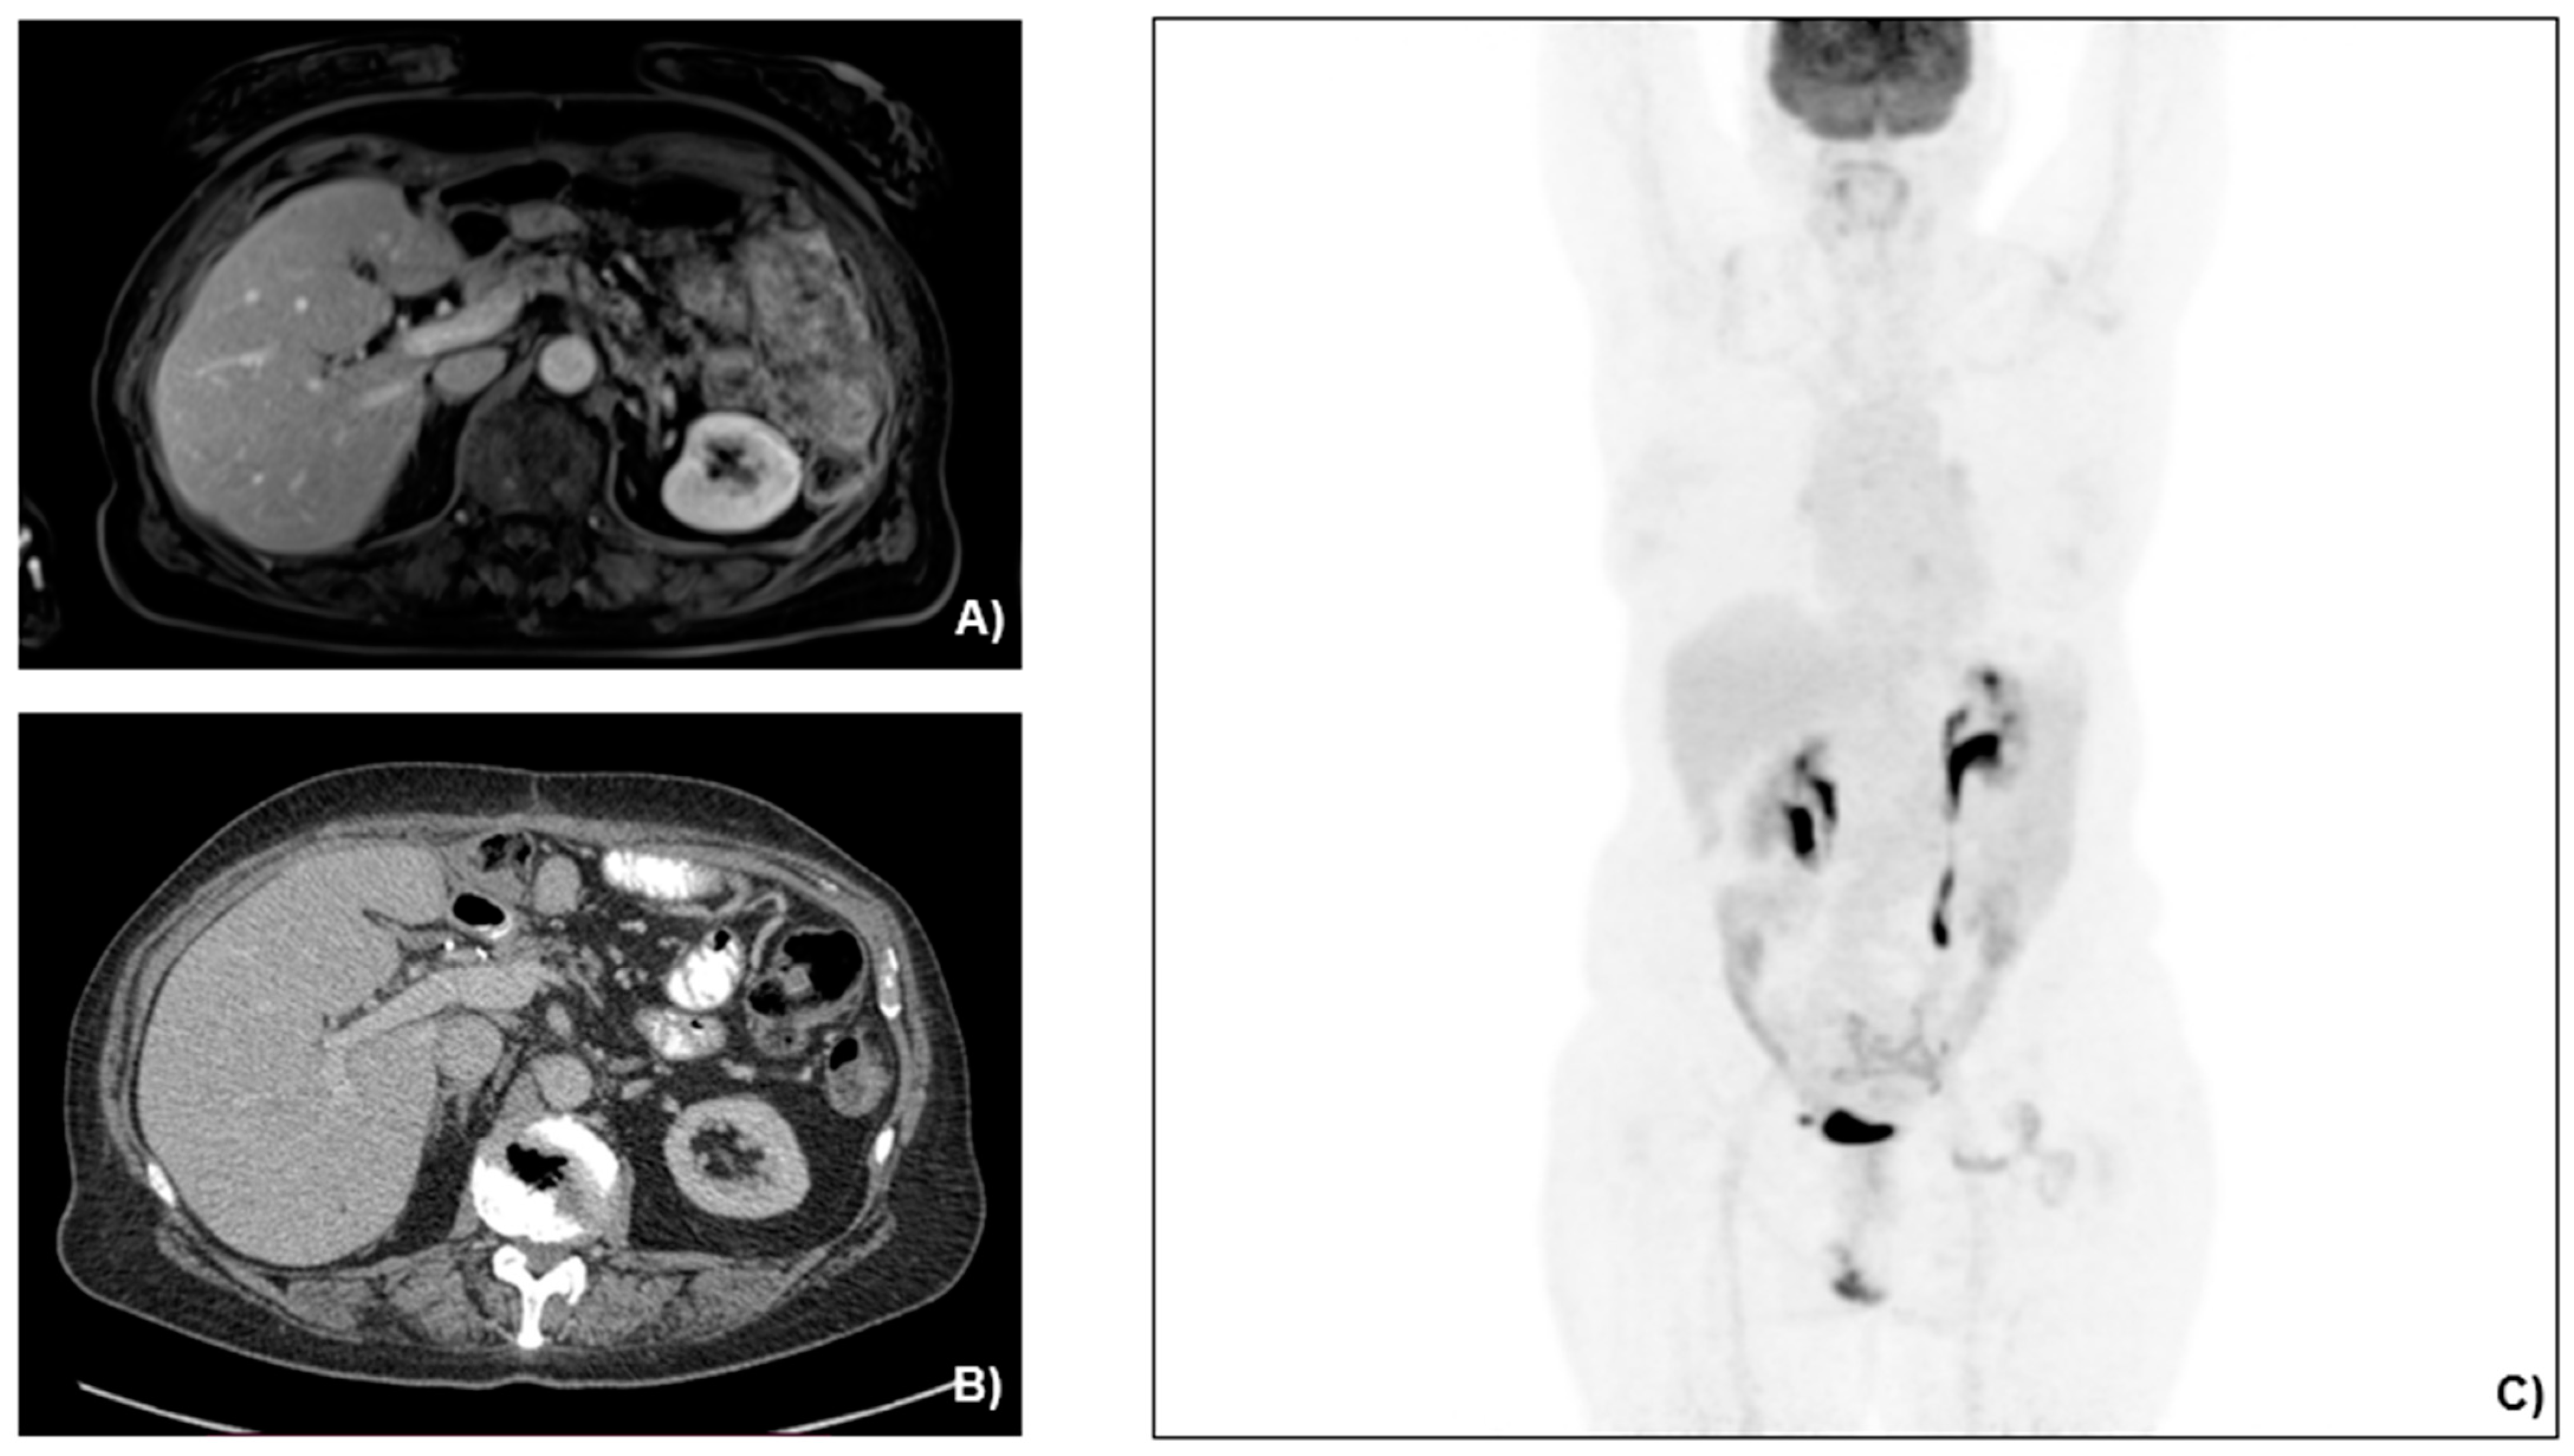

2.2. Case Presentation

3.1. Case Management